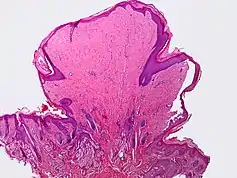

A skin tag, or acrochordon (pl. acrochorda), is a small benign tumor that forms primarily in areas where the skin forms creases (or rubs together), such as the neck, armpit and groin. They may also occur on the face, usually on the eyelids. Though tags up to half an inch (12.7 mm) long have been seen,[2] they are typically the size of a grain of rice. The surface of an acrochordon may be smooth or irregular in appearance and is often raised from the surface of the skin on a fleshy stalk called a peduncle. Microscopically, an acrochordon consists of a fibrovascular core, sometimes also with fat cells, covered by an unremarkable epidermis. However, tags may become irritated by shaving, clothing, jewellery or eczema.